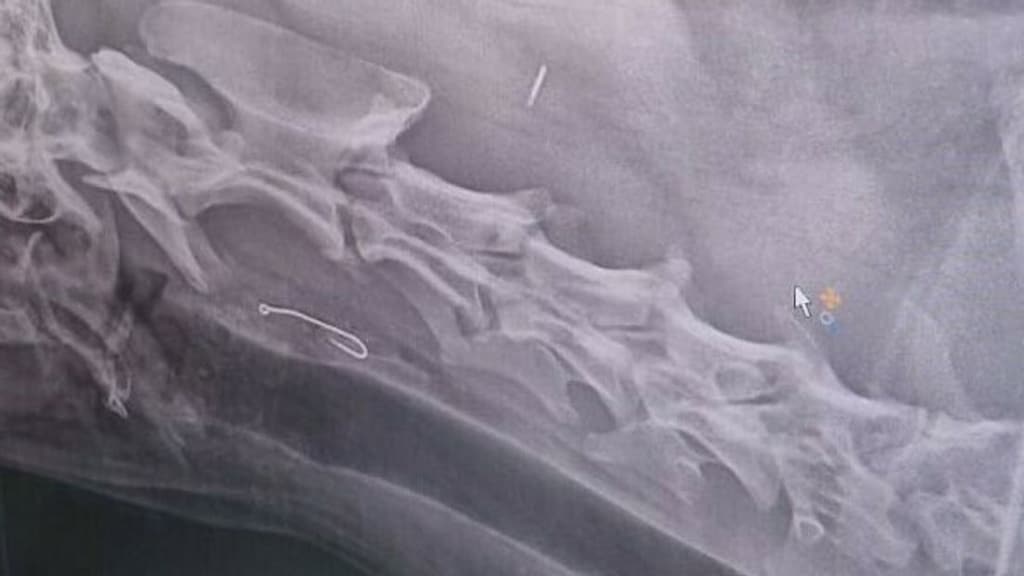

Valster is op dat moment op het Zeeuwse strand in de buurt Kamperland. Ze belt de dierenarts en kan meteen terecht in Goes. "De hele rit zat ik te trillen." Op de röntgenfoto blijkt de haak vast te zitten in zijn slokdarm. Twee uur lang probeert de dierenarts het eruit te krijgen met een tang, maar zonder resultaat.

Django moet vervolgens onder narcose mee in de auto naar het dierenziekenhuis in Roosendaal. Daar staat een specialist klaar die met een speciale tang nog een laatste poging doet. "Na 45 minuten kwam hij hoofdschuddend terug: te gevaarlijk. De haak zit te diep. Alleen een operatie via een incisie in de hals kan nog helpen", schrijft Valster op Facebook als ze thuiskomt, zonder Django.